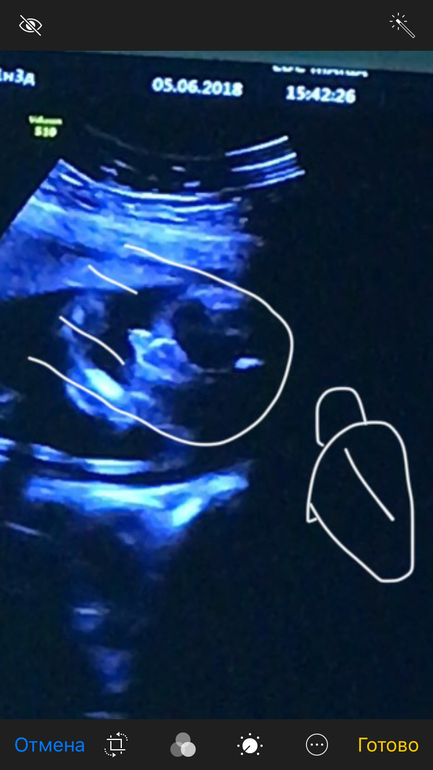

Узи. 22нед МАЛЬЧИК или ДЕВОЧКА?

Пол малышаНа стоп кадрах узи есть и пирожок и перчик🤣

Я делала на тел запись при узи и прям по секундам его пересмотрела, и что вы думаете.... с разницей в полсекунды там и пирожок и писюн🤷♀️

Смотрите сами) кто что видит???